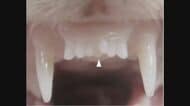

有田玲子医師:目から紫外線を浴びることは、様々な病気につながります。目が炎症を起こすことで涙が蒸発しやすくなって「ドライアイ」になったり、スキー場や海水浴場で強い紫外線を浴びて角膜が傷つく「電気性眼炎」などもよくあるケースです。これらは治療をすればある程度回復するのですが、そうはいかないものもあります。

50代以上の多くの人がかかる「白内障」も、紫外線によって発症・進行します。紫外線により水晶体がダメージを受けると、もう元には戻らないのです。外で働く職業やスポーツ選手などは、早くに白内障を発症するというデータもあり、白内障が紫外線の影響を大きく受けることが分かっています。